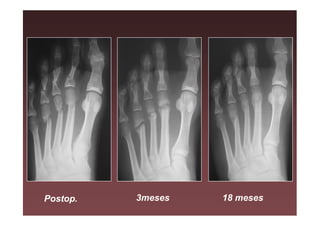

Postop.   3meses   18 meses